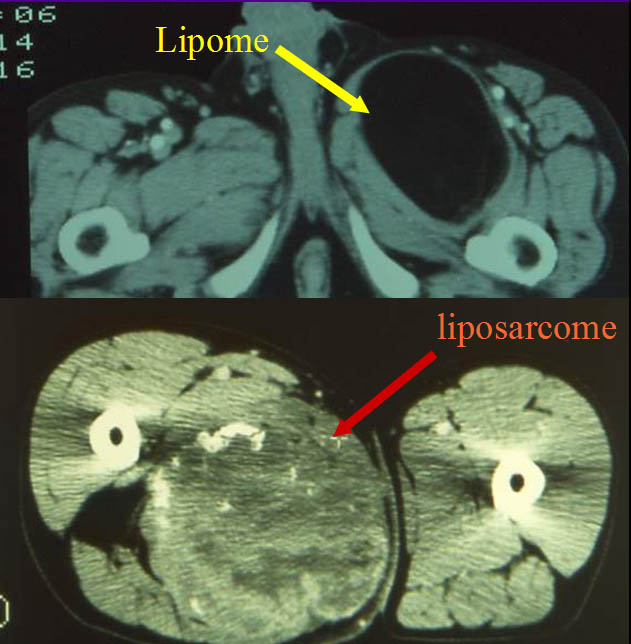

TDM, Lipomes et Liposarcomes

Le lipome se présente, en effet, comme une tumeur homogène de densité fortement négative (-70 à -30).

L'existence de certaines plages avec une densité cellulaire (30) doit faire soupçonner le liposarcome.